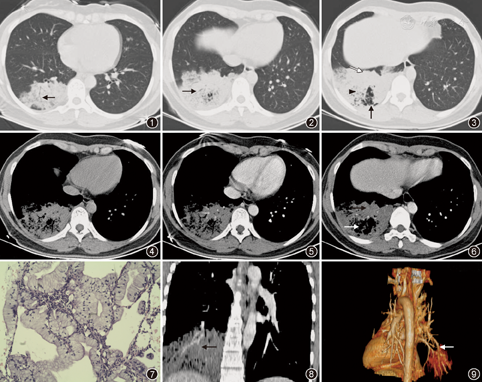

入院后血气分析示:血液pH值7.380,二氧化碳分压36.0 mmHg,氧分压89.0 mmHg,碳酸氢根浓度21.0 mmol/L,二氧化碳总量22.0 mmol/L,氧饱和度97.0%;血常规白细胞8.3×109/L,中性粒细胞0.64;癌胚抗原0.30 μg/L(正常参考值为0~5.00 μg/L);C反应蛋白为0.85 mg/L;血生化检查未见异常;真菌葡聚糖真菌(1,3)-β-D葡聚糖<5.0 ng/L;两便常规正常;多次痰涂片找抗酸杆菌及痰涂片找癌细胞均阴性;抗核抗体谱阴性;抗中性粒细胞胞质抗体系列阴性。2013年7月21日胸部增强CT显示:右下肺可见大片密度增高影,密度不均,增强扫描其内可见较多血管影,病灶强化不明显;余肺未见明显实质性病灶;各支气管腔通畅,肺门及纵隔未见明显增大淋巴结;胸膜未见明显增厚;胸腔无积液(图1,图2,图3,图4,图5,图6)。

入院后考虑患者外院已行抗感染治疗2周以上疗效不佳,2013年7月22日在CT引导下行右肺经皮肺穿刺病理示:肺泡内衬瘤细胞,乳头状,具有黏液细胞特征,胞质丰富透亮,核偏位,轻度异型;病理确诊右肺腺癌(图7)。确诊后于2013年8月1日在胸外科行手术治疗,术后病理诊断为右下肺浸润性黏液腺癌,淋巴结转移阴性,免疫组织化学:TTF1(+)、CK7(+)、CK20(+)、MUC-2(-)。

仔细阅读分析高分辨率胸部CT的影像学表现也有助于鉴别诊断。本例患者从影像学表现分析应当属于肺炎型肺腺癌。本例患者CT影像学整体表现为肺段实变伴空泡及蜂窝状影,周围为边缘不清的云絮状阴影,病灶的实质CT值偏低,强化不明显,平扫纵隔窗肺实质CT值25 Hu,增强扫描后CT值38 Hu,增强值13 Hu,强化不明显(图4,图5)。实变影由癌细胞及癌细胞分泌的黏液大部分或完全充填肺泡造成;癌细胞沿肺泡孔及细支气管播散蔓延及继发出血和炎性渗出形成周围的模糊的云絮状阴影。此外,还具有以下影像学特征:(1)癌性充气支气管征:是本病与细菌性炎症及肺栓塞鉴别的要点之一[1];癌细胞沿气道表面生长,造成支气管僵直、狭窄、壁锯齿状或伴支气管腔内毛刺;或由于癌细胞沿肺泡壁生长伴肺泡壁塌陷,导致远端支气管受压迫闭塞,形成充气支气管的截断。本例患者胸部高分辨率CT肺窗显示充气支气管僵直、狭窄,远端支气管截断不能显影(图1,图2)。(2)叶间胸膜膨隆:肿瘤细胞分泌的黏液使肺叶膨胀、叶间裂膨隆,叶间裂膨隆可呈锯齿状或弧形隆起;该征象在大叶性肺炎或肺不张很少见。本例患者胸部高分辨CT肺窗显示右下肺后短叶间裂呈锯齿状隆起(图3),体现肿瘤的浸润和膨胀性生长的特点。(3)空泡征或假性空洞征:未被肿瘤组织占据的含气组织;未闭合或扩张的小支气管;肿瘤细胞沿管壁生长使管腔形成活瓣样阻塞,气体进入肺泡腔但难以排出致肺泡腔过度充气表现为小空泡征或假空洞征。本例患者胸部高分辨CT肺窗显示较多气体密度或低密度空泡征,部分形成囊样空泡或假性空洞样表现(图3),极易和肺脓肿空洞混淆。(4)CT血管征:血管树未被肺癌所侵蚀扭曲及由于大量黏液的产生,实变的肺组织在增强时密度较血管低,从而导致增强扫描时血管纹理显影清晰[2]。本例患者胸部增强CT重建显示右下肺血管走行纹理清晰光滑,未见明显扭曲变形(图8),血管纹和低密度实变形成明显对比,为CT血管征;血管重建显示右下肺肿瘤组织包绕血管,但血管纹理清晰,走行流畅,无扭曲变形(图9)。虽然血管造影征对黏液腺癌诊断有提示作用但不具有特异性,但结合其他影像学特点综合分析对诊断有较大的提示作用。